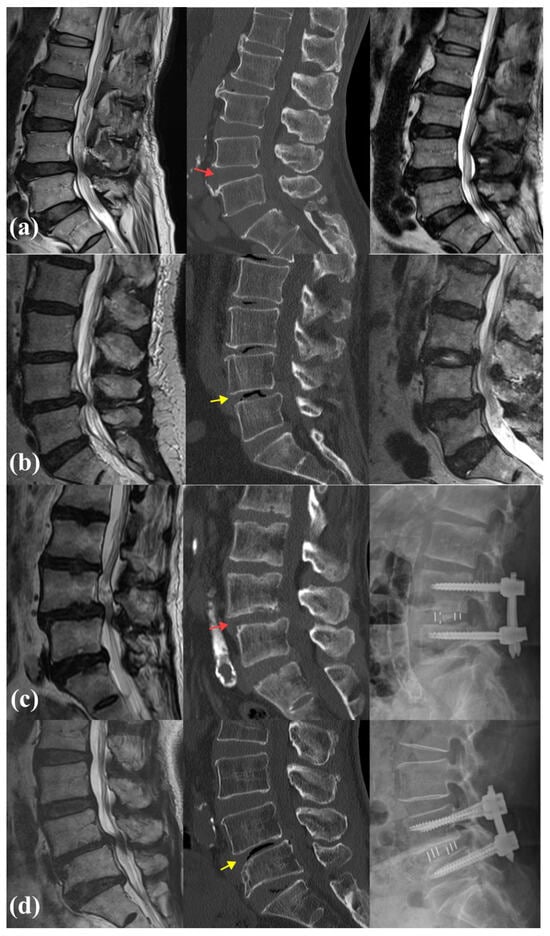

4. Representative Cases